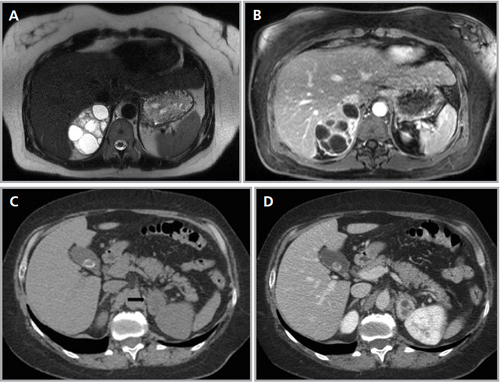

Las lesiones de mayor tamaño con frecuencia presentan componentes quísticos debido a necrosis central o hemorragia antigua (Figura 25 a, b, c y d).

Figura 25. Feocromocitoma quístico. Cortes axiales de resonancia magnética (a) ponderado en T2 secuencia HASTE y (b) ponderado en T1 con saturación grasa y uso de contraste ev. Se identifica una lesión sólido-quística suprarrenal derecha, marcadamente hiperintensa en secuencias ponderadas en T2 y con significativo refuerzo de sus septos con el uso de contraste. Otro caso (c) y (d) cortes axiales de TC donde se demuestra una lesión suprarrenal izquierda (flecha), que también presenta áreas hipodensas centrales determinadas por focos de degeneración quística.

En cuanto a la etiología de las lesiones suprarrenales en la población general, las cifras promedio que se han reportado en varias series se distribuyen aproximadamente de la siguiente manera: 41% correspondería a adenomas, 10% a metástasis, 10% carcinoma adrenocortical, 9% mielolipomas, 8% feocromocitomas, y otras lesiones tales como linfoma, quistes, hemorragia, ganglioneuromas, hemangiomas y enfermedad granulomatosa darían cuenta del porcentaje restante3.